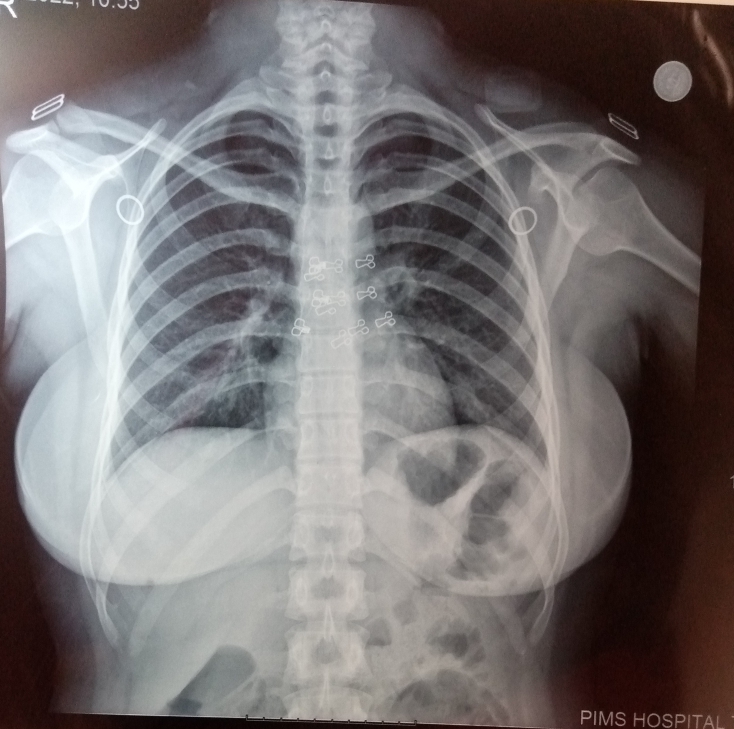

I have cough 4 months ,doctor prescribed following medicines , Myteka and rigix. I also have done with RFT ,LFT and are the results that are attached below , Is there any problem?